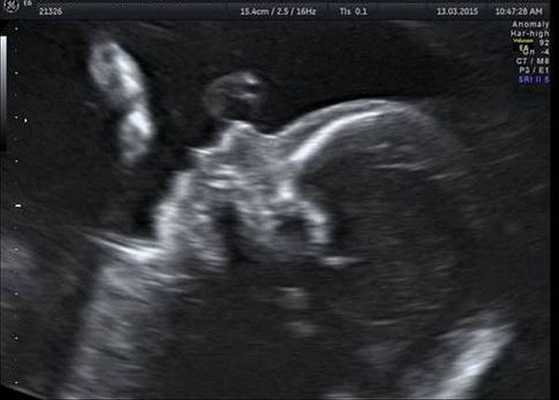

Как правило, диагностировать синдром Гольденхара не составляет труда. Постановка этого диагноза основана на оценке внешних признаков, клинической симптоматике и результатах дополнительных исследований — КТ, рентгенографии, МСКТ черепа, эхокардиографии и ультразвуковой диагностики. КТ, как правило, проводится для подготовки ребёнка к оперативному лечению.

Индивидуальная профилактика синдрома предполагает проведение медико-генетического консультирования семьи и пренатальной ультразвуковой диагностики беременной женщины в установленные сроки [12] .